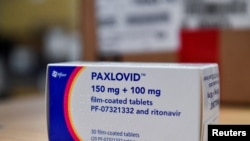

Paxlovid has become the go-to option against COVID-19 because of its at-home convenience and impressive results in heading off severe disease. The U.S. government has spent more than $10 billion to purchase enough pills to treat 20 million people.

But experts say there is still much to be learned about the drug, which was authorized in December for adults at high risk of severe COVID-19 based on a study in which 1,000 adults received the medication.

Charness says Paxlovid remains a highly effective drug, but he wonders if it might be less potent against the current omicron variant. The $500 drug treatment was tested and approved based on its performance against the delta version of the coronavirus.

Pfizer tested Paxlovid in the highest-risk patients: unvaccinated adults with no prior COVID-19 infection and other health problems, such as heart disease and diabetes. The drug reduced their risk of hospitalization and death from 7% to 1%.